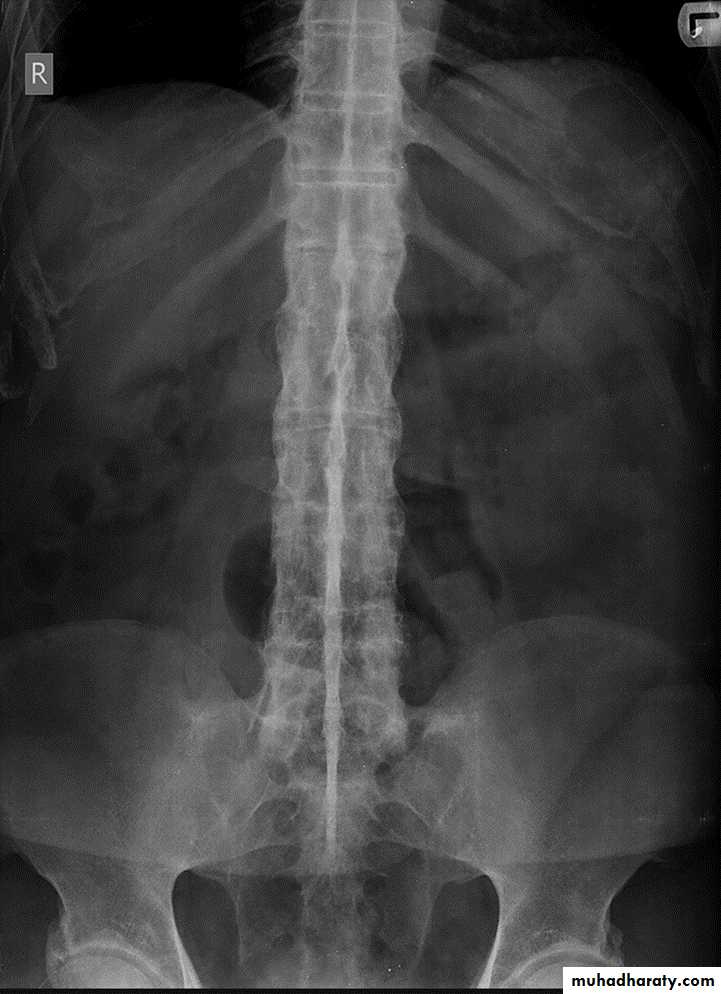

DIFFUSE IDIOPATHIC SKELETAL HYPEROSTOSIS (DISH)

Radiographic features:*Flowing osteophytes of at least four contiguous vertebral bodies

*Preserved disk height

*No sacroiliitis or facet ankylosis

*Calcification of ligaments and tendons

*Associated with hypertrophic DJD